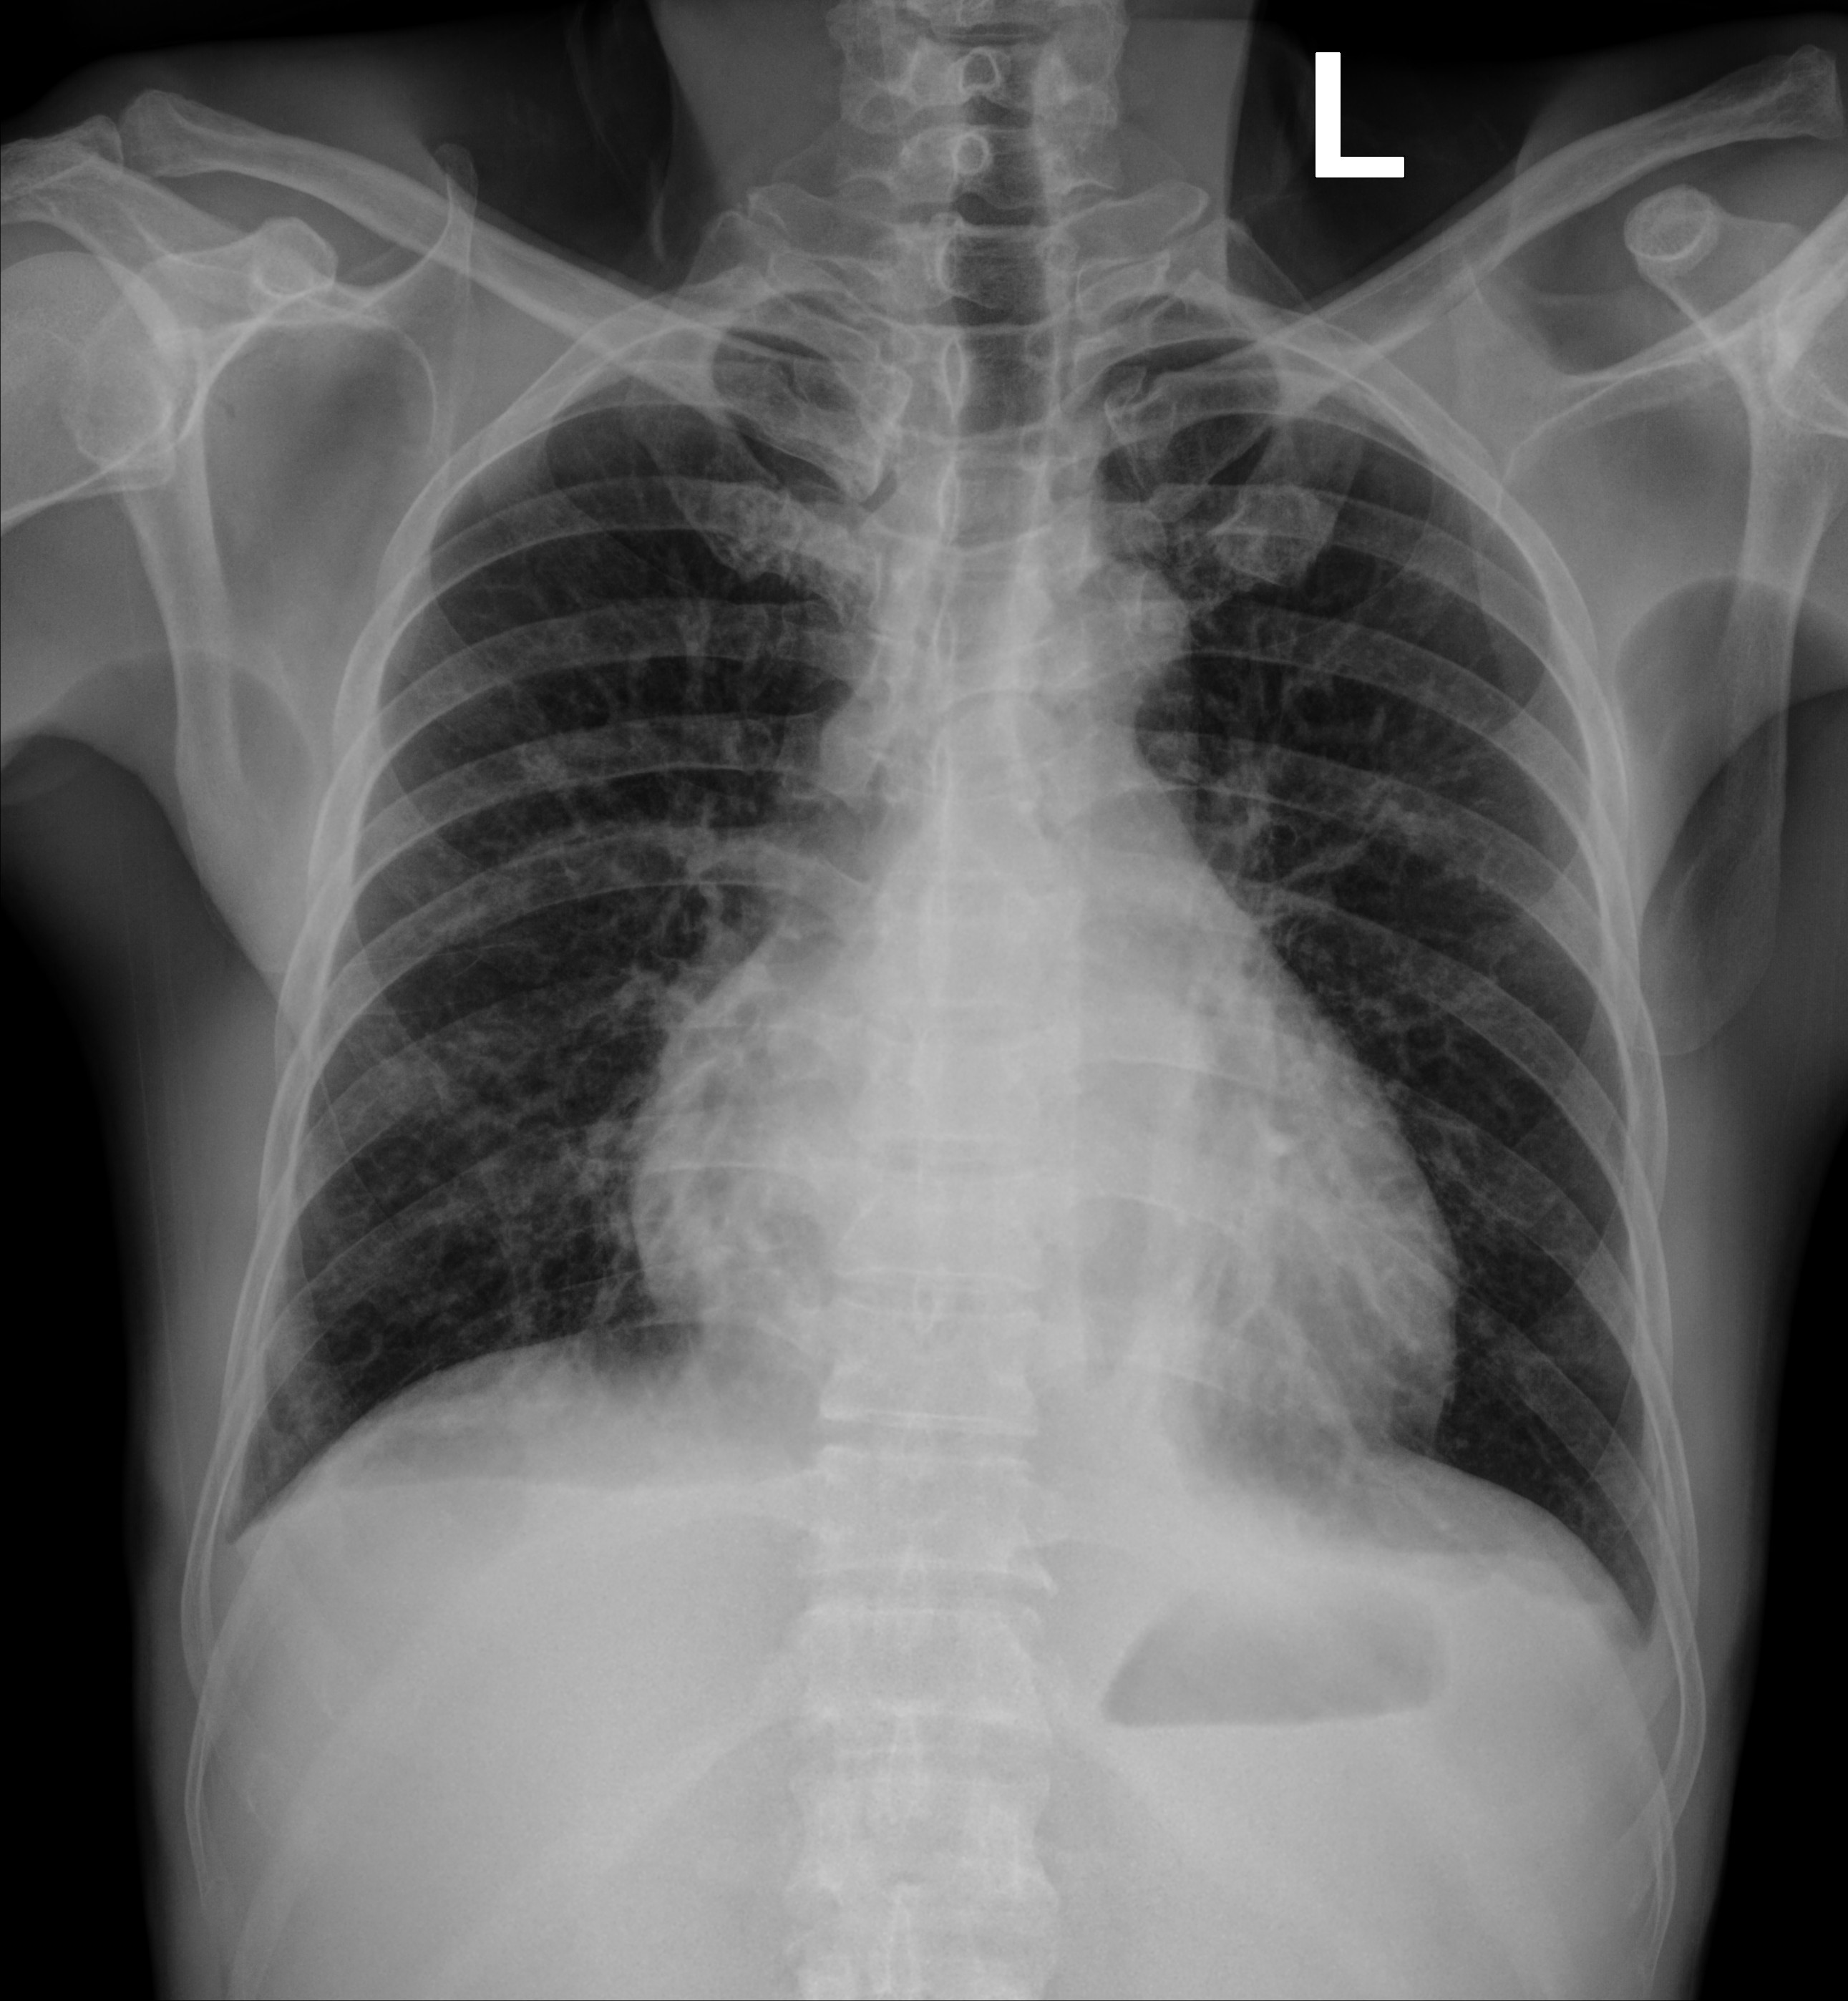

Bệnh nhân Chu Đ.C., nam 52 tuổi, quê Phú Thọ, được chuyển xuống Bệnh viện Bạch Mai ngày 20/10/2025 vì chảy máu mũi nhiều, điều trị tuyến trước không dứt. Vào viện, người bệnh được làm xét nghiệm máu và tủy, được chẩn đoán Bệnh bạch cầu cấp dòng tủy (AML-M6) kèm nhiễm trùng tiết niệu, rối loạn đông máu. X-quang ngực chụp buổi sáng cho thấy hai trường phổi sạch, tràn dịch màng phổi nhẹ, nghĩa là phổi lúc đó hoàn toàn “trong”.

Ảnh: Phim chụp Xquang phổi của bệnh nhân C.Đ.C (21/10) và CT scan (24/10)